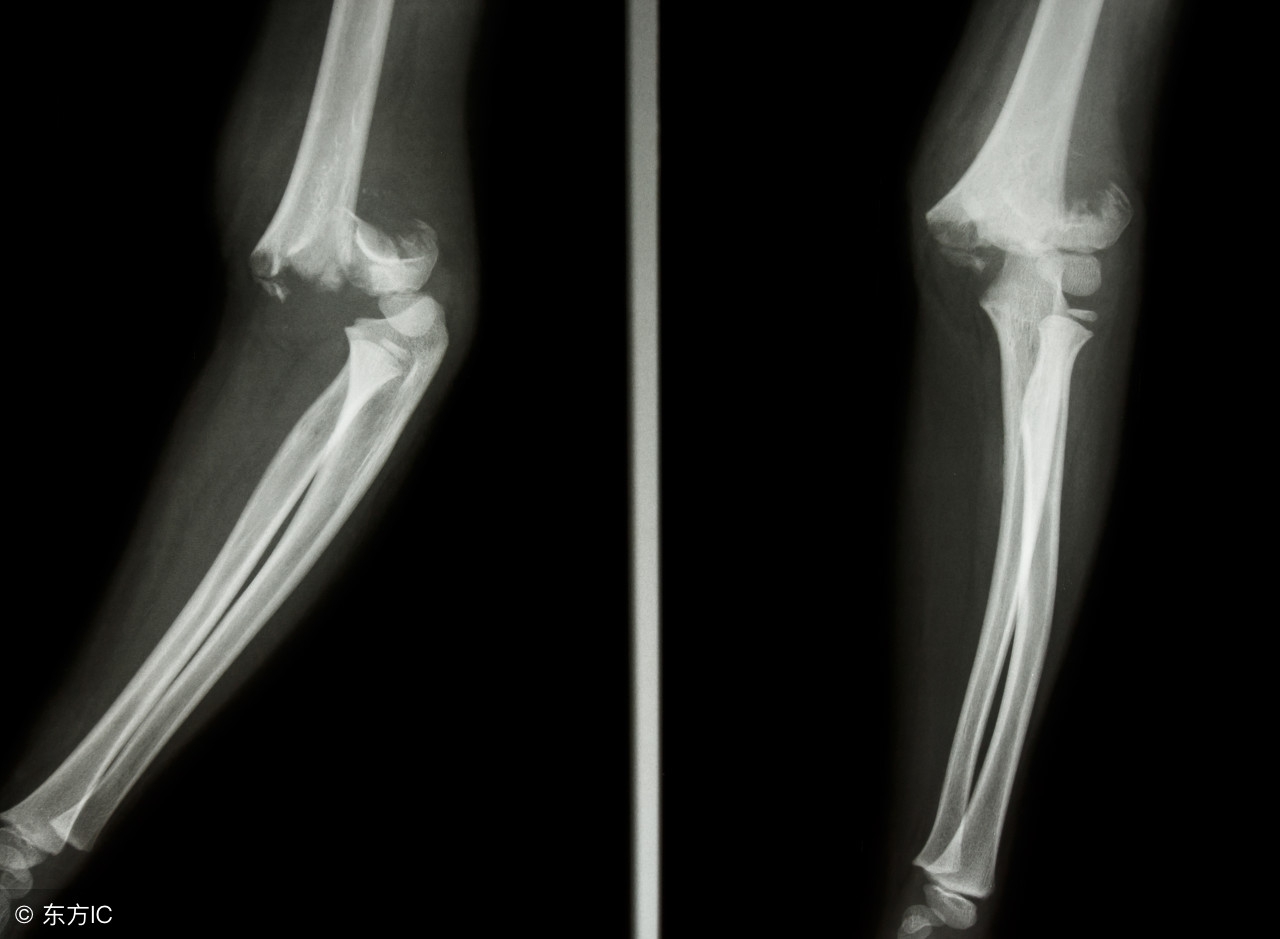

(2)骨折打石膏有一周了,怎么拍片子骨折缝更大了?

骨头断了的同时,骨折断端会有很多细小的碎骨渣,这些骨渣失去了血液供应,属于没有活性的骨头了。并且,骨头折断处骨质也会因为血管损坏而失去血供。大脑会认为这些失去血运的组织是失活的坏死的东西,而命令体内打扫战场的细胞来把它们清理掉。大约一周左右的时间,这些骨折缝隙处的骨碎屑,骨折断端处没有血供的骨质就会被清理细胞吸收掉。所以在X片上看起来,骨折缝反而比刚骨折时候更宽些。不要担心,这是正常现象。

(3)为什么我手术后的X片上看,骨折并没有对的严丝合缝,医生却告诉我没问题?

第一个条件是复位:骨折当然是对的严丝合缝最好,所谓解剖复位,就是骨折对位对的和原来一样。但是又一个问题,有的病人是粉碎性骨折,根本没法对成原来的样子,甚至想要对合80%都有困难。俗话说,破镜难重圆,要求骨科医生把一堆骨折渣拼成像原装的一样,只能说“来,你来拼试试”。除了难拼,还有一个问题就是手术不可能像在家里修东西一样,想修多长时间就修多长时间,病人在打着麻药,伤口在流着血,止血带有时间限制,暴露在空气中的伤口表面在飘落着细菌,有的还是老年病人,每多一分钟,各种风险发生几率就增加一分。所以骨折的手术讲究的是在最短的时间内尽可能的把骨折复位到满意的位置。当然了,对于“满意的位置”,也是有原则有规定的,由于我们的骨头愈合能力非常强大,有些部位对位对上三分之一,就能愈合。而基本对上70~80%,就能愈合的很好。当然,对于关节面的要求是很严格的,尽可能解剖复位,不然以后发生创伤性关节炎的可能性会增大。(即使对的100%完美,也依然可能发生创伤性关节炎)。十年以前,骨折治疗领域非常强调解剖复位,现在理念有所改进,比起解剖复位,更看中骨折周围血运的保护,因为过度追求解剖复位,势必造成手术时间延长,手术对骨折部位的干扰增加,这种对血供的影响,现在认为比骨折100%复位还要重要。因为越来越多的病例证实,即使100%复位,也会有一些人骨折不愈合,骨不连,就是因为血供不佳造成的。这种血供不佳可能源于骨折受伤的一瞬间,血管损伤严重;也可能源于手术中对血管的二次破坏;也可能源于骨折的部位本来就皮包骨头,血供差;也可能源于抽烟等影响血管生长的原因。所以,对于粉碎性骨折,如果你的术后片子上骨折对位并不是严丝合缝,其实也并不一定有多大问题,照样能长的很好,如果是用的微创技术和髓内钉技术,那更是不太可能解剖复位的,因为这些技术本身就是牺牲一些对位来换取对骨折部位血供的最小破坏。